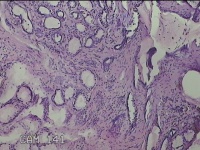

左侧外阴囊肿壁

性别

女

年龄

35岁

临床诊断

左外阴囊肿

一般病史

发现外阴囊肿2年余,加重3月。

标本名称

大体所见

灰白暗红色囊壁样组织5.5x2.8x0.7cm一堆,表面光滑,部分已切开,囊内容物已流失,囊壁厚0.1cm。

图2

具体位置,考虑巴氏腺囊肿。